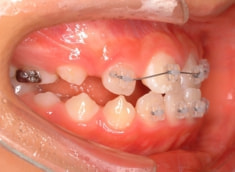

治療法:上顎拡大装置+フルパッシブブラケット(クリアスナップ)+フェイスマスク等

治療開始から3ヶ月後